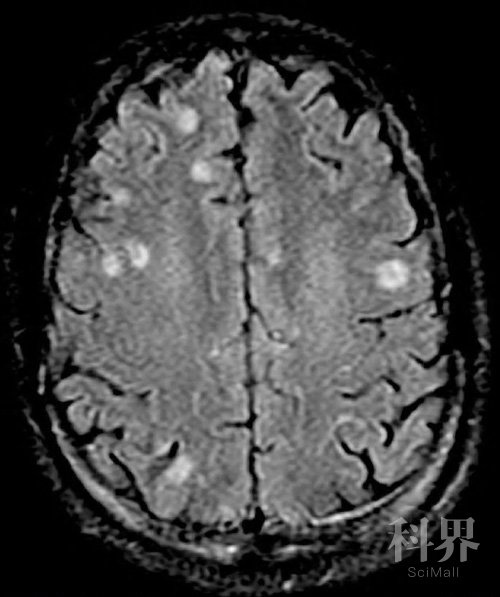

弓形虫在人脑内形成的囊肿(白色部位)丨来源:#:Oit_c3_d04.png